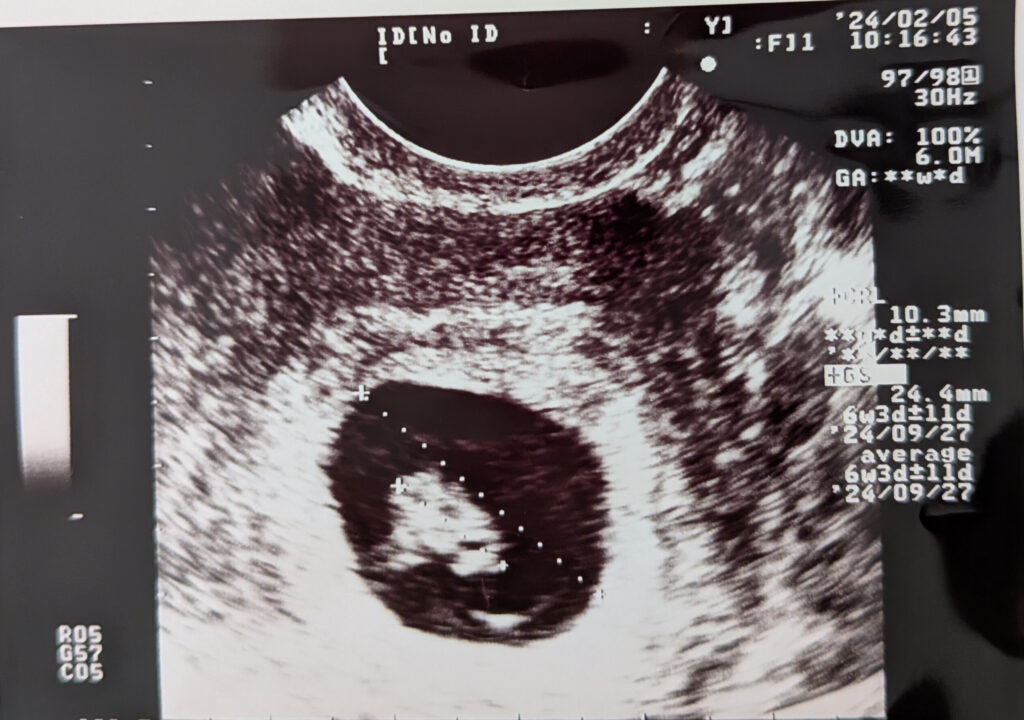

次に受診したのは6週0日。エコーに映ったのは、

胎嚢(GS)11mm、胎芽(CRL)2.7mm

の小さな命でした。

胎嚢は24.4mm、赤ちゃん(胎芽)は10.3mmまで成長し、

心拍も確認できたのです。